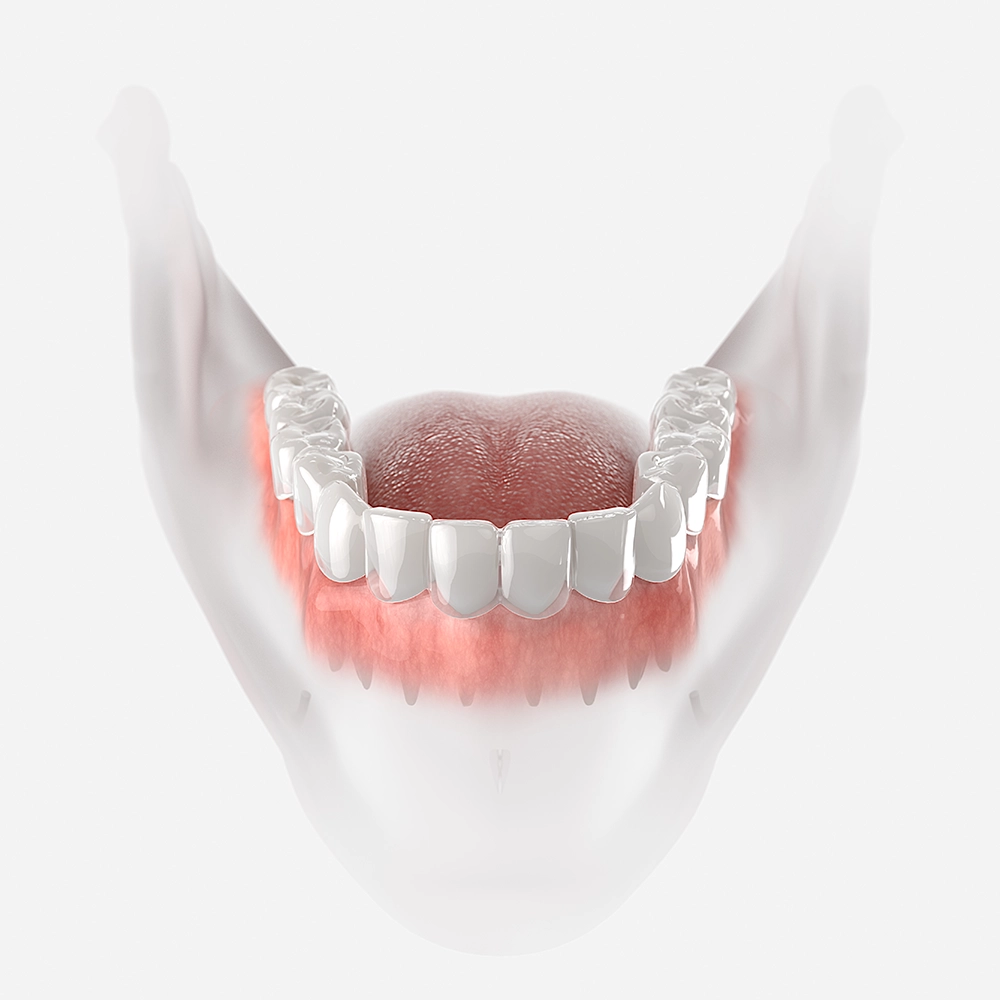

Misaligned jaws can make everyday activities like eating feel frustrating and uncomfortable. Patients may struggle to chew effectively, which can lead to digestive issues and lower quality of life. Corrective jaw surgery restores proper alignment, making eating more comfortable and enjoyable. Choosing Maine Oral Surgery & Dental Implant Center gives you the opportunity to reclaim functional oral health and confidence during meals.